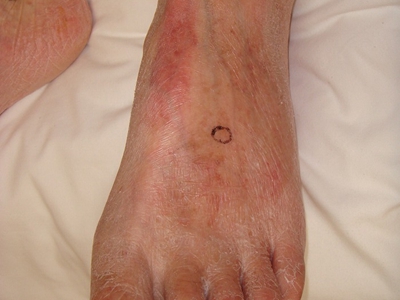

闭塞性动脉硬化症脚部有红斑以及黑斑图

以上为闭塞性动脉硬化症脚部有红斑以及黑斑图。

闭塞性动脉硬化症的损害可发生在脚部,临床上可表现为脚部皮肤温度降低,并出现颜色及营养性变化,皮肤颜色发红呈红斑状,有点状暗黑斑,患者因足部疼痛而出现间歇性跛行。